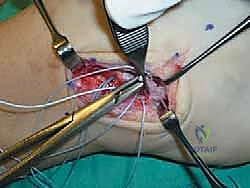

الخطوة الخامسة: زراعة خطاطيف الخياطة (Suture Anchors)

هنا تتجلى التقنيات الحديثة. بدلاً من حفر ثقوب كبيرة في العظم كما كان يحدث قديماً، يستخدم أ.د. محمد هطيف خطاطيف دقيقة جداً (Suture Anchors) مصنوعة من مواد متوافقة حيوياً (Bio-composite) أو التيتانيوم. يتم زرع خطاف أو خطافين في عظمة الشظية، وتكون هذه الخطاطيف محملة بخيوط جراحية فائقة القوة.

الخطوة السادسة: خياطة وشد الأربطة (إجراء بروسترم الأساسي)

يتم تمرير الخيوط الجراحية القوية عبر الأربطة الممزقة (ATFL و CFL) والكبسولة المفصلية. أثناء عقد هذه الخيوط، يتم وضع الكاحل في وضعية الانقلاب الخارجي (Eversion) والانعطاف الظهري (Dorsiflexion) لضمان شد الأربطة بأقصى درجة ممكنة، مما يعيد للكاحل ثباته الفوري.

الخطوة السابعة: تعديل جولد (The Gould Modification) - سر القوة الإضافية

لضمان عدم تكرار التمزق، خاصة للرياضيين، يضيف الجراح خطوة "تعديل جولد". تتمثل هذه الخطوة في سحب جزء من النسيج الليفي القوي المجاور والمسمى بـ "القيد الباسط السفلي" (Inferior Extensor Retinaculum) وخياطته فوق الأربطة التي تم إصلاحها. يعمل هذا النسيج كـ "حزام أمان" إضاف